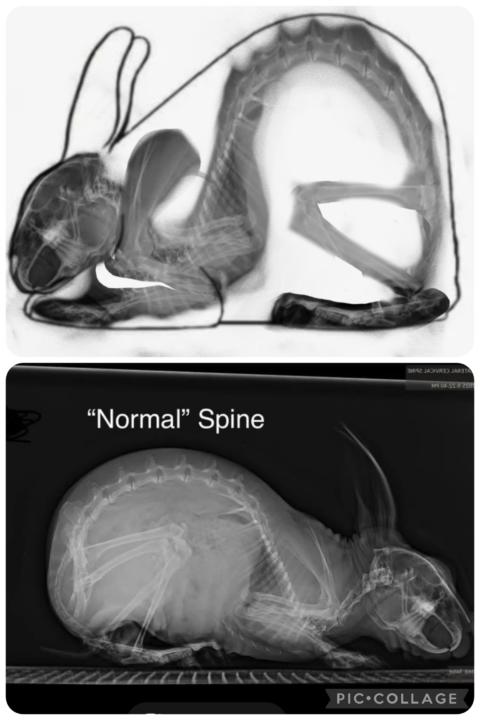

I strongly dislike this illustration. It isn’t based on actual rabbit anatomy or skeletal alignment—it reflects a narrow aesthetic preference that became popular, not a structurally sound model. When this outline is selected for, it produces a “chopped” hindquarter, forces the pelvis to tuck under, and narrows the pelvic outlet. That combination predictably leads to reproductive and structural problems, including a pinched birth canal and compromised locomotion. The placement of the high point is the core issue. In this illustration it’s pushed too far back, effectively over the pelvic joint. In a correctly aligned skeleton, the high point falls just behind the knee, not over the pelvis. You can see this clearly when you overlay a naturally positioned skeleton. In the X-ray example below, the feet are slightly overposed, but once you visualize the alignment, the topline matches correctly—and the high point lands where anatomy dictates, not where a few people say it should be. This illustration has been overused, unchallenged, and repeated long past the point where it should have been corrected. When layered over real skeletal structure, it simply doesn’t hold up.